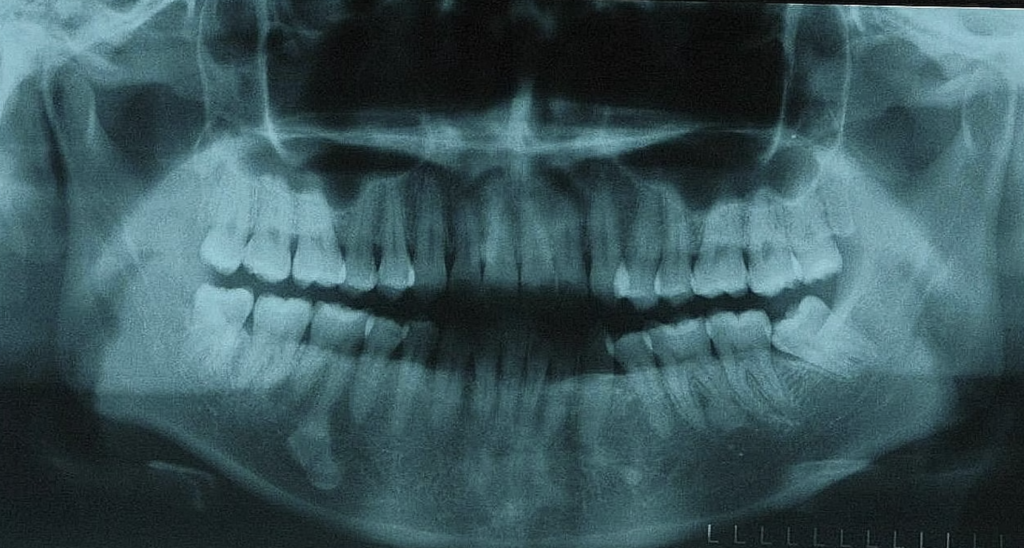

Dengan menggunakan sinar-X, doktor gigi juga akan menilai keadaan tulang dan tahap kerosakan yang terlibat.

Pelbagai faktor boleh mempengaruhi kos prosedur ini, termasuk jenis dan tahap kesulitan himpitan gigi, sama ada penggunaan ubat bius umum diperlukan, dan lokasi tempat tinggal anda.

Menurut Kementerian Kesihatan Malaysia, berikut adalah harga purata bagi prosedur pencabutan gigi bongsu:

- RM15 bagi setiap gigi bongsu yang mudah dicabut, di mana gigi telah tumbuh sepenuhnya dengan akar yang pendek, dan prosedur ini hanya memerlukan penggunaan ubat bius setempat.

- RM50 bagi setiap gigi bongsu yang terhimpit, tetapi masih boleh dicabut dengan penggunaan ubat bius setempat. Jenis himpitan gigi juga boleh mempengaruhi harga, dengan cabutan gigi yang hanya meletus separuh jalan biasanya lebih murah berbanding dengan gigi yang terbenam sepenuhnya dalam tulang rahang.

Ini termasuklah kos sinar-x gigi, yang juga dikenali sebagai radiograf, yang purata harganya sekitar RM10.